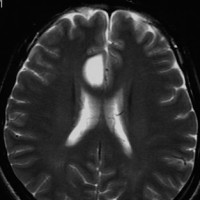

T2-FLAIR mismatch sign (T2とフレアの信号が違うこと)

protoplasmic astrocytomaに特徴的なMRI所見です。T2強調画像(左側)では白く(強い均一な高信号)見えます。でもフレア画像(右側)では白く縁取ったように見えます。びまん性星細胞腫の大きな特徴とされます。内部がとても柔らかいドロドロした腫瘍のこともあります。